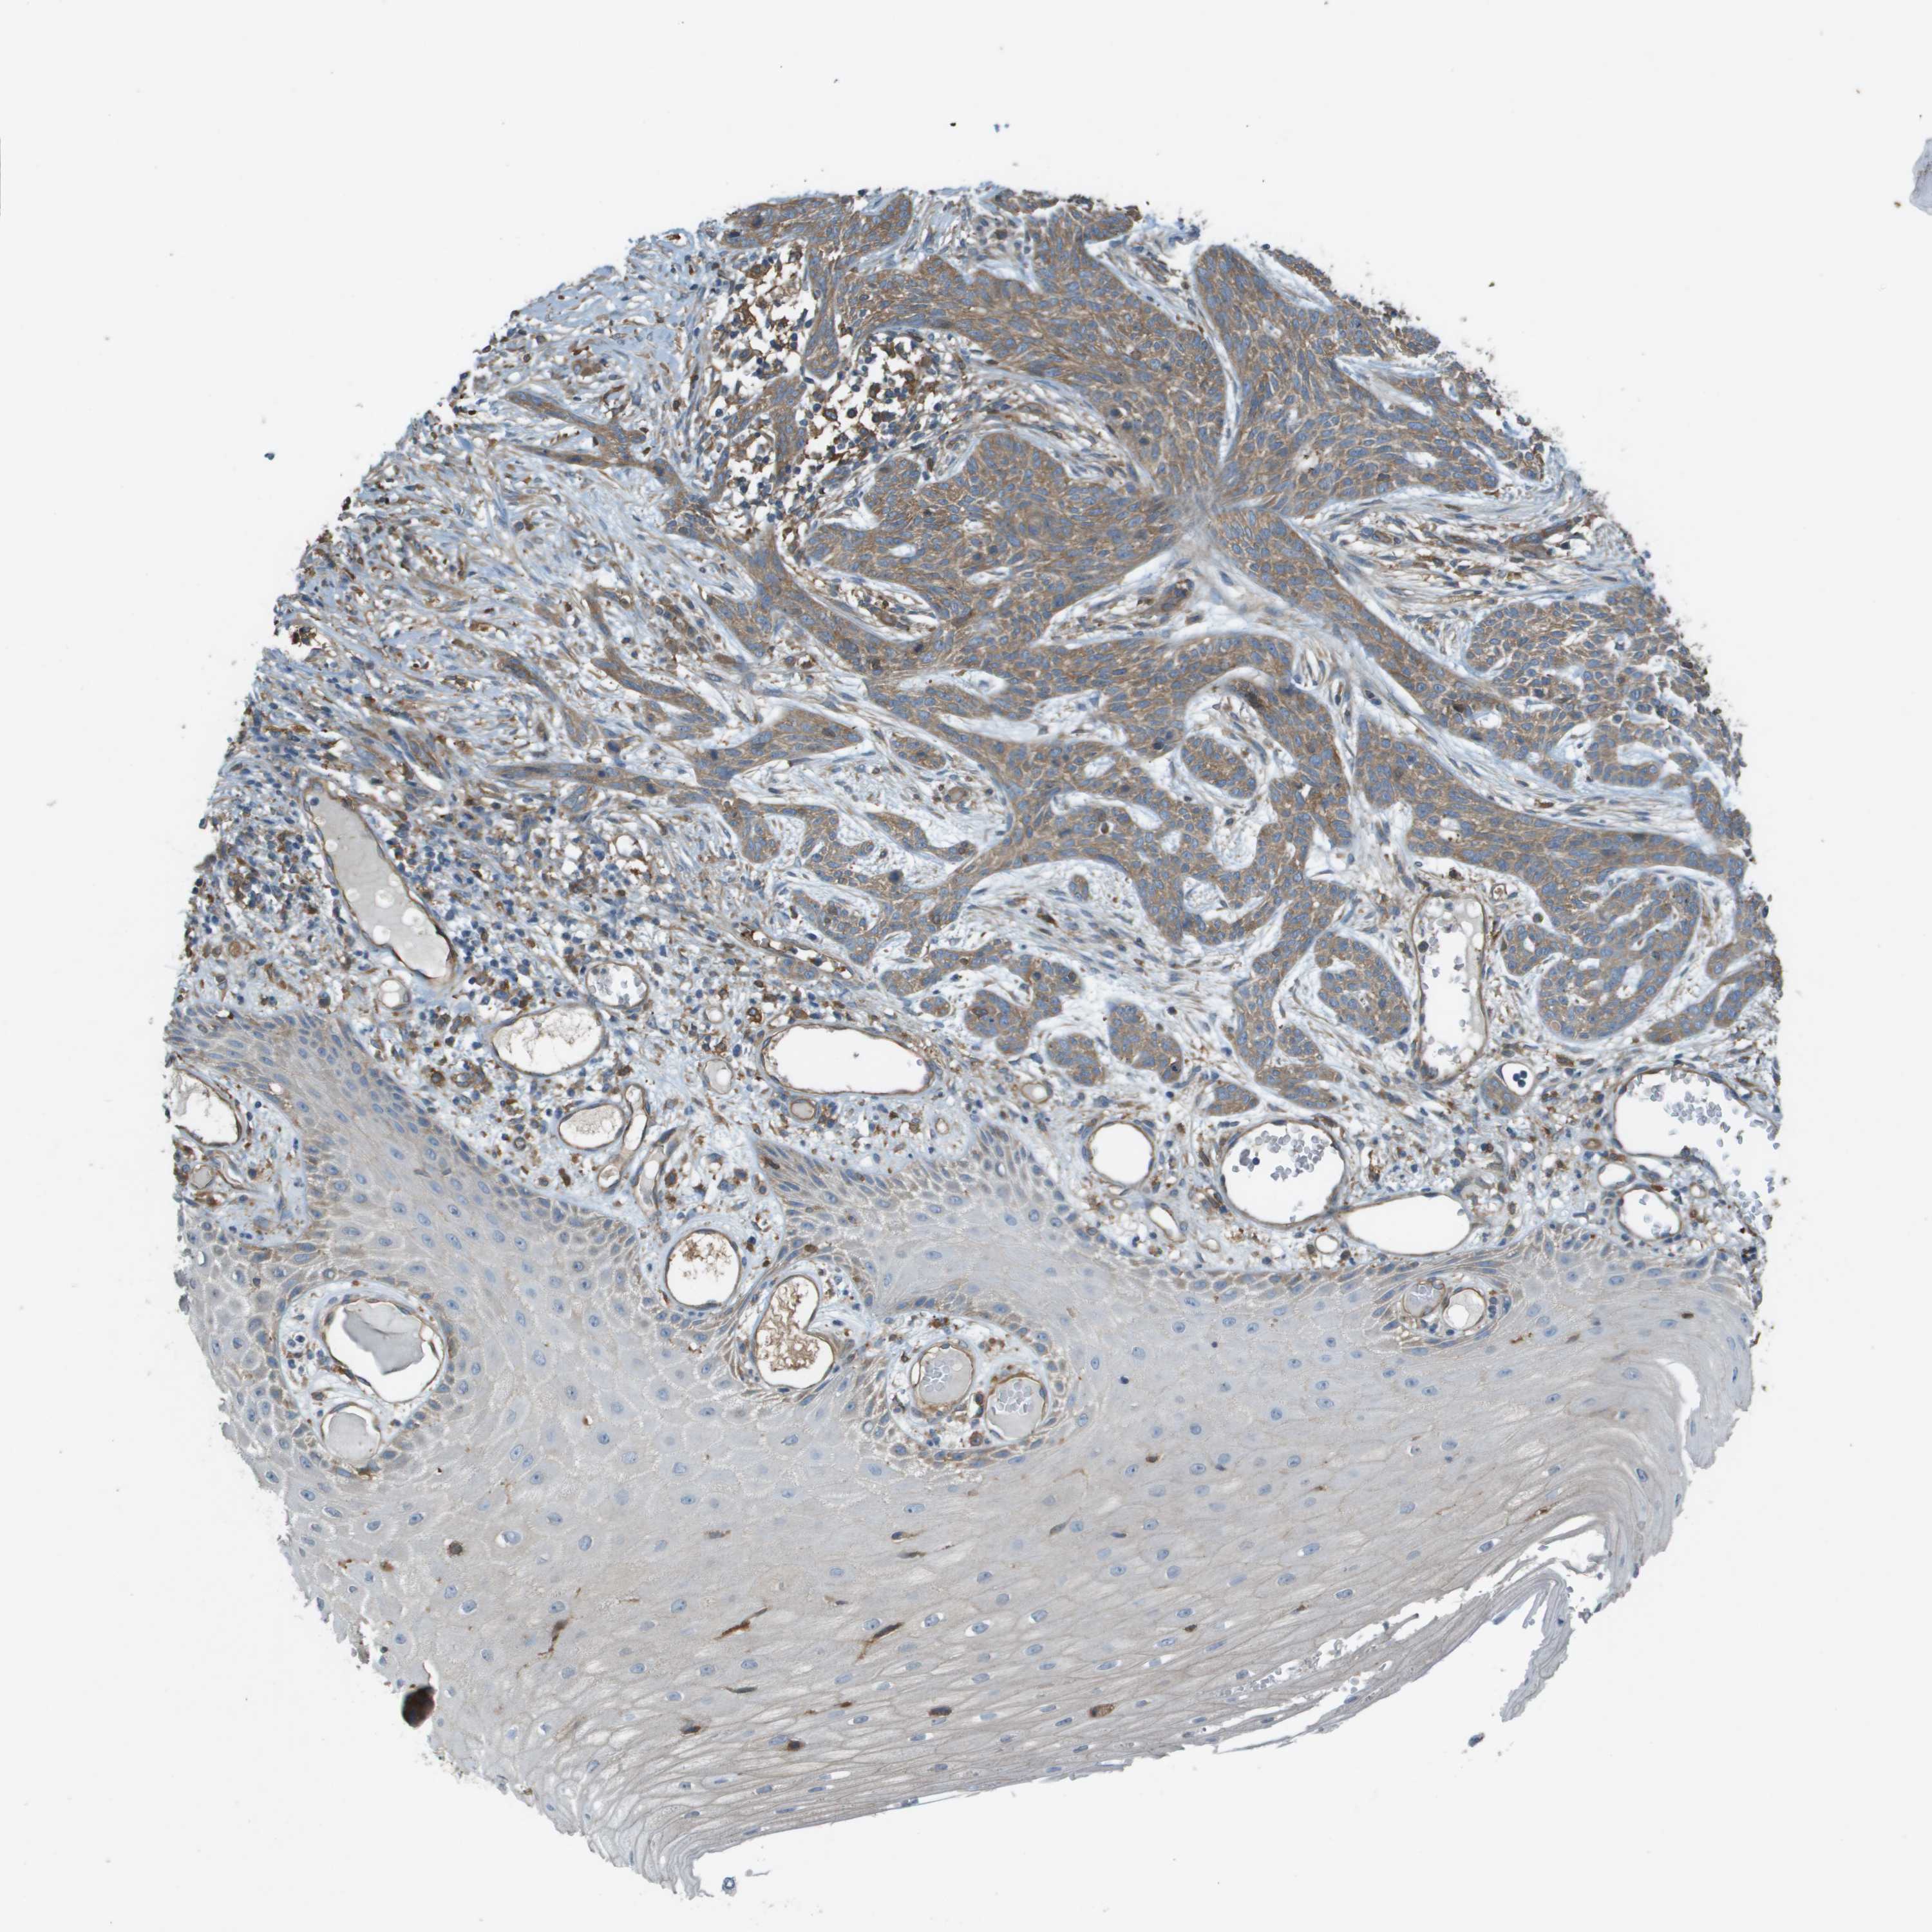

SKIN CANCER - Protein expressioni

A mouse-over function shows sample information and annotation data. Click on an image to view it in a full screen mode. Samples can be filtered based on level of antibody staining by selecting one or several of the following categories: high, medium, low and not detected. The assay and annotation is described here.

Antibody stainingi

Antibody staining in the annotated cell types in the current human tissue is reported as not detected, low, medium, or high, based on conventional immunohistochemistry profiling in selected tissues. This score is based on the combination of the staining intensity and fraction of stained cells.

Each image is clickable and will lead to virtual microscopy that enables deeper exploration of all samples and also displays staining intensity scores, fraction scores and subcellular localization as well as patient and tissue information for each sample.

Antibody HPA070456

Antibody CAB017616

Staining

High

Medium

Low

Not detected

Intensity

Strong

Moderate

Weak

Negative

Quantity

>75%

75%-25%

<25%

None

Location

Nuclear

Cytoplasmic/membranous

Cytoplasmic/membranous,nuclear

Basal cell carcinoma

Squamous cell carcinoma, NOS

Squamous cell carcinoma in situ, NOS

Adnexal tumor, benign